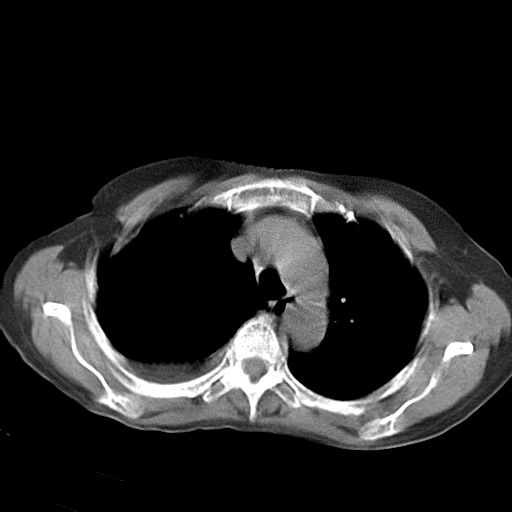

以下是引用dyqct在2006-12-7 21:08:00的发言:[br]考虑:1、肝内外胆管多发性结石伴肝左叶外侧段肝萎缩;[br] 2、右膈下多发脓肿;[br] 3、右侧少量胸腔积液、斜裂积液;[br] 4、左肾囊肿。

以下是引用拾荒者在2006-12-7 21:44:00的发言:[br]肝内外胆管多发结石,右膈下多发脓肿,右胸膜腔及叶间裂积液,左肾囊肿。[br] [br]